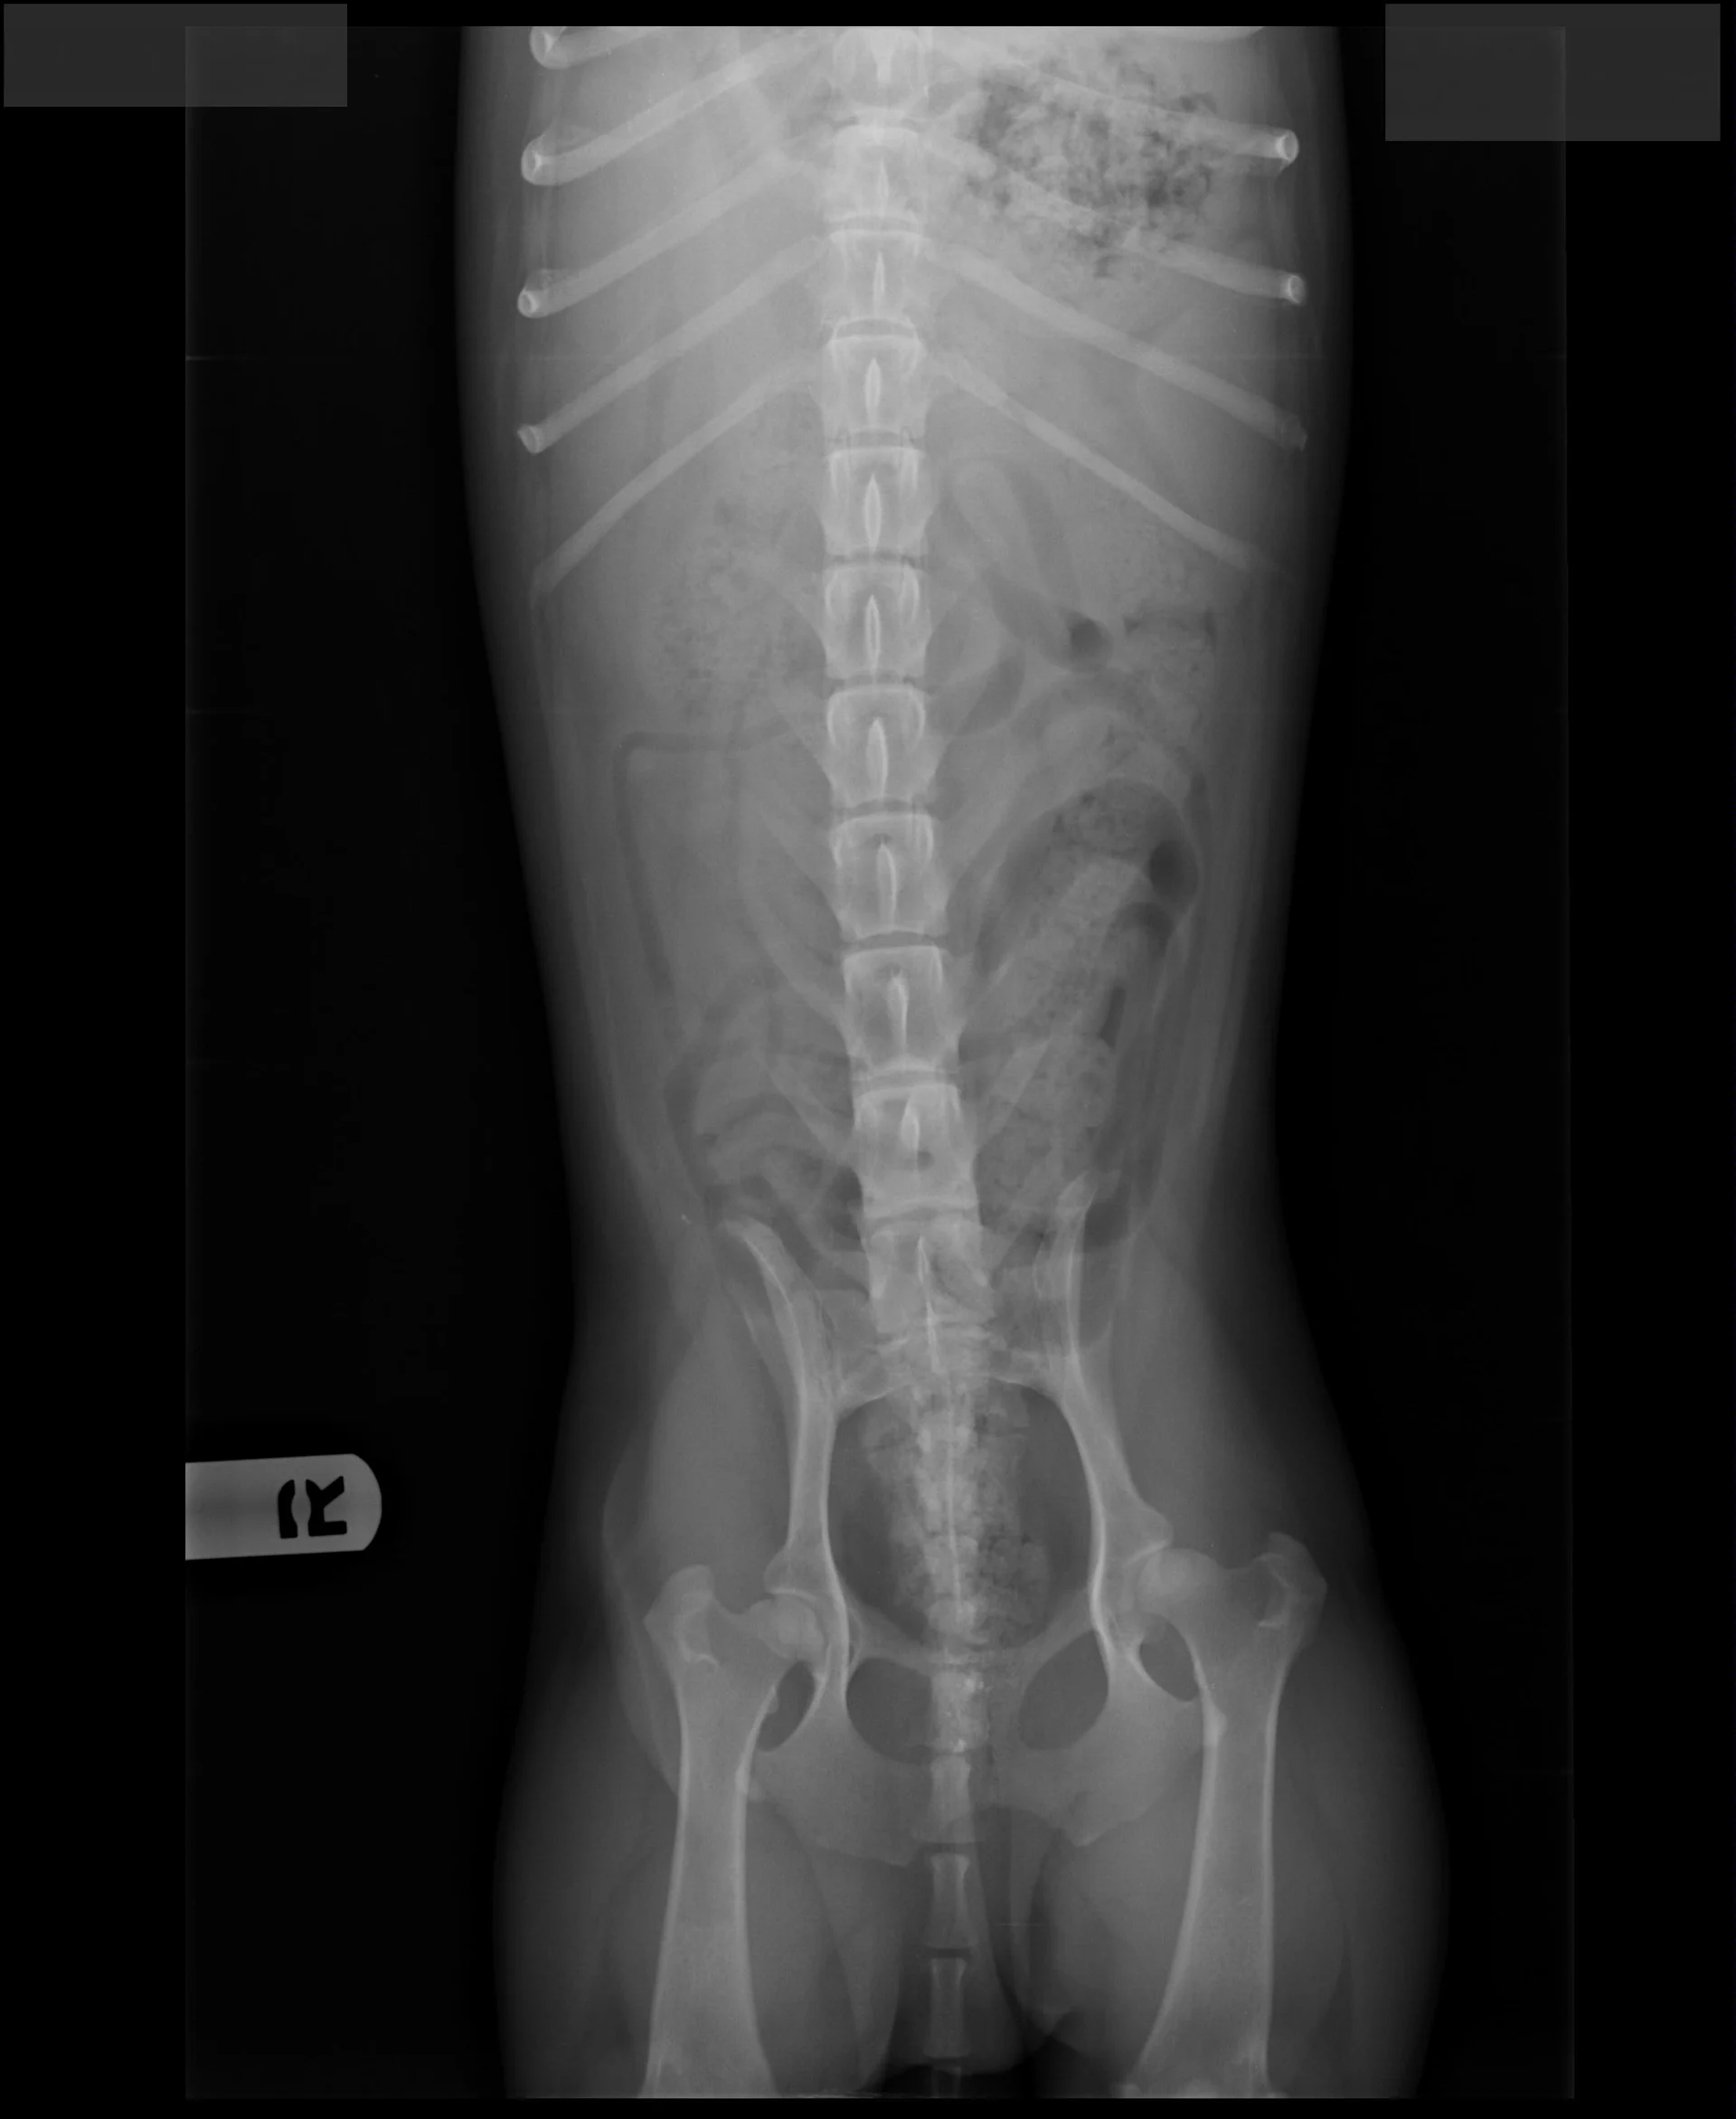

FIGURE 1

Radiographs of Ernest at 8 years of age at a recheck examination